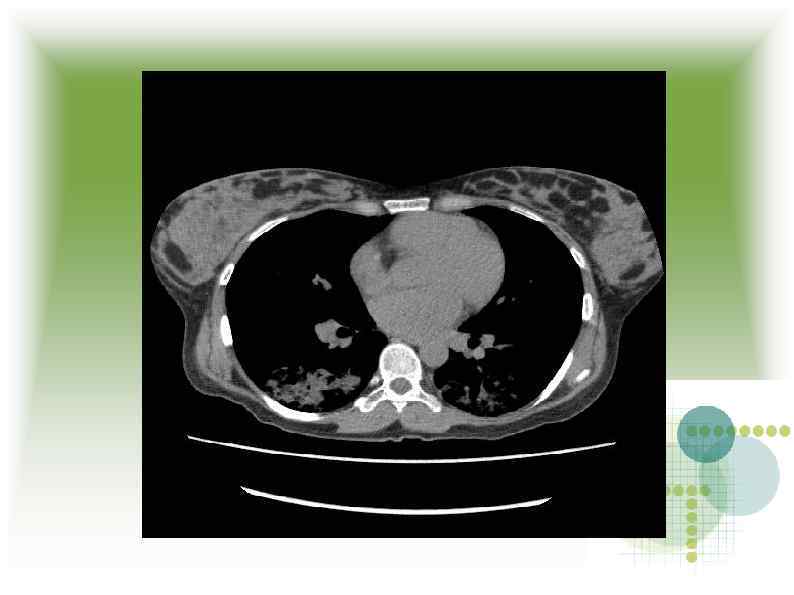

МСКТ МСКТ

Заключение МСКТ Признаки геморрагической пневмонии? Заключение МСКТ Признаки геморрагической пневмонии?